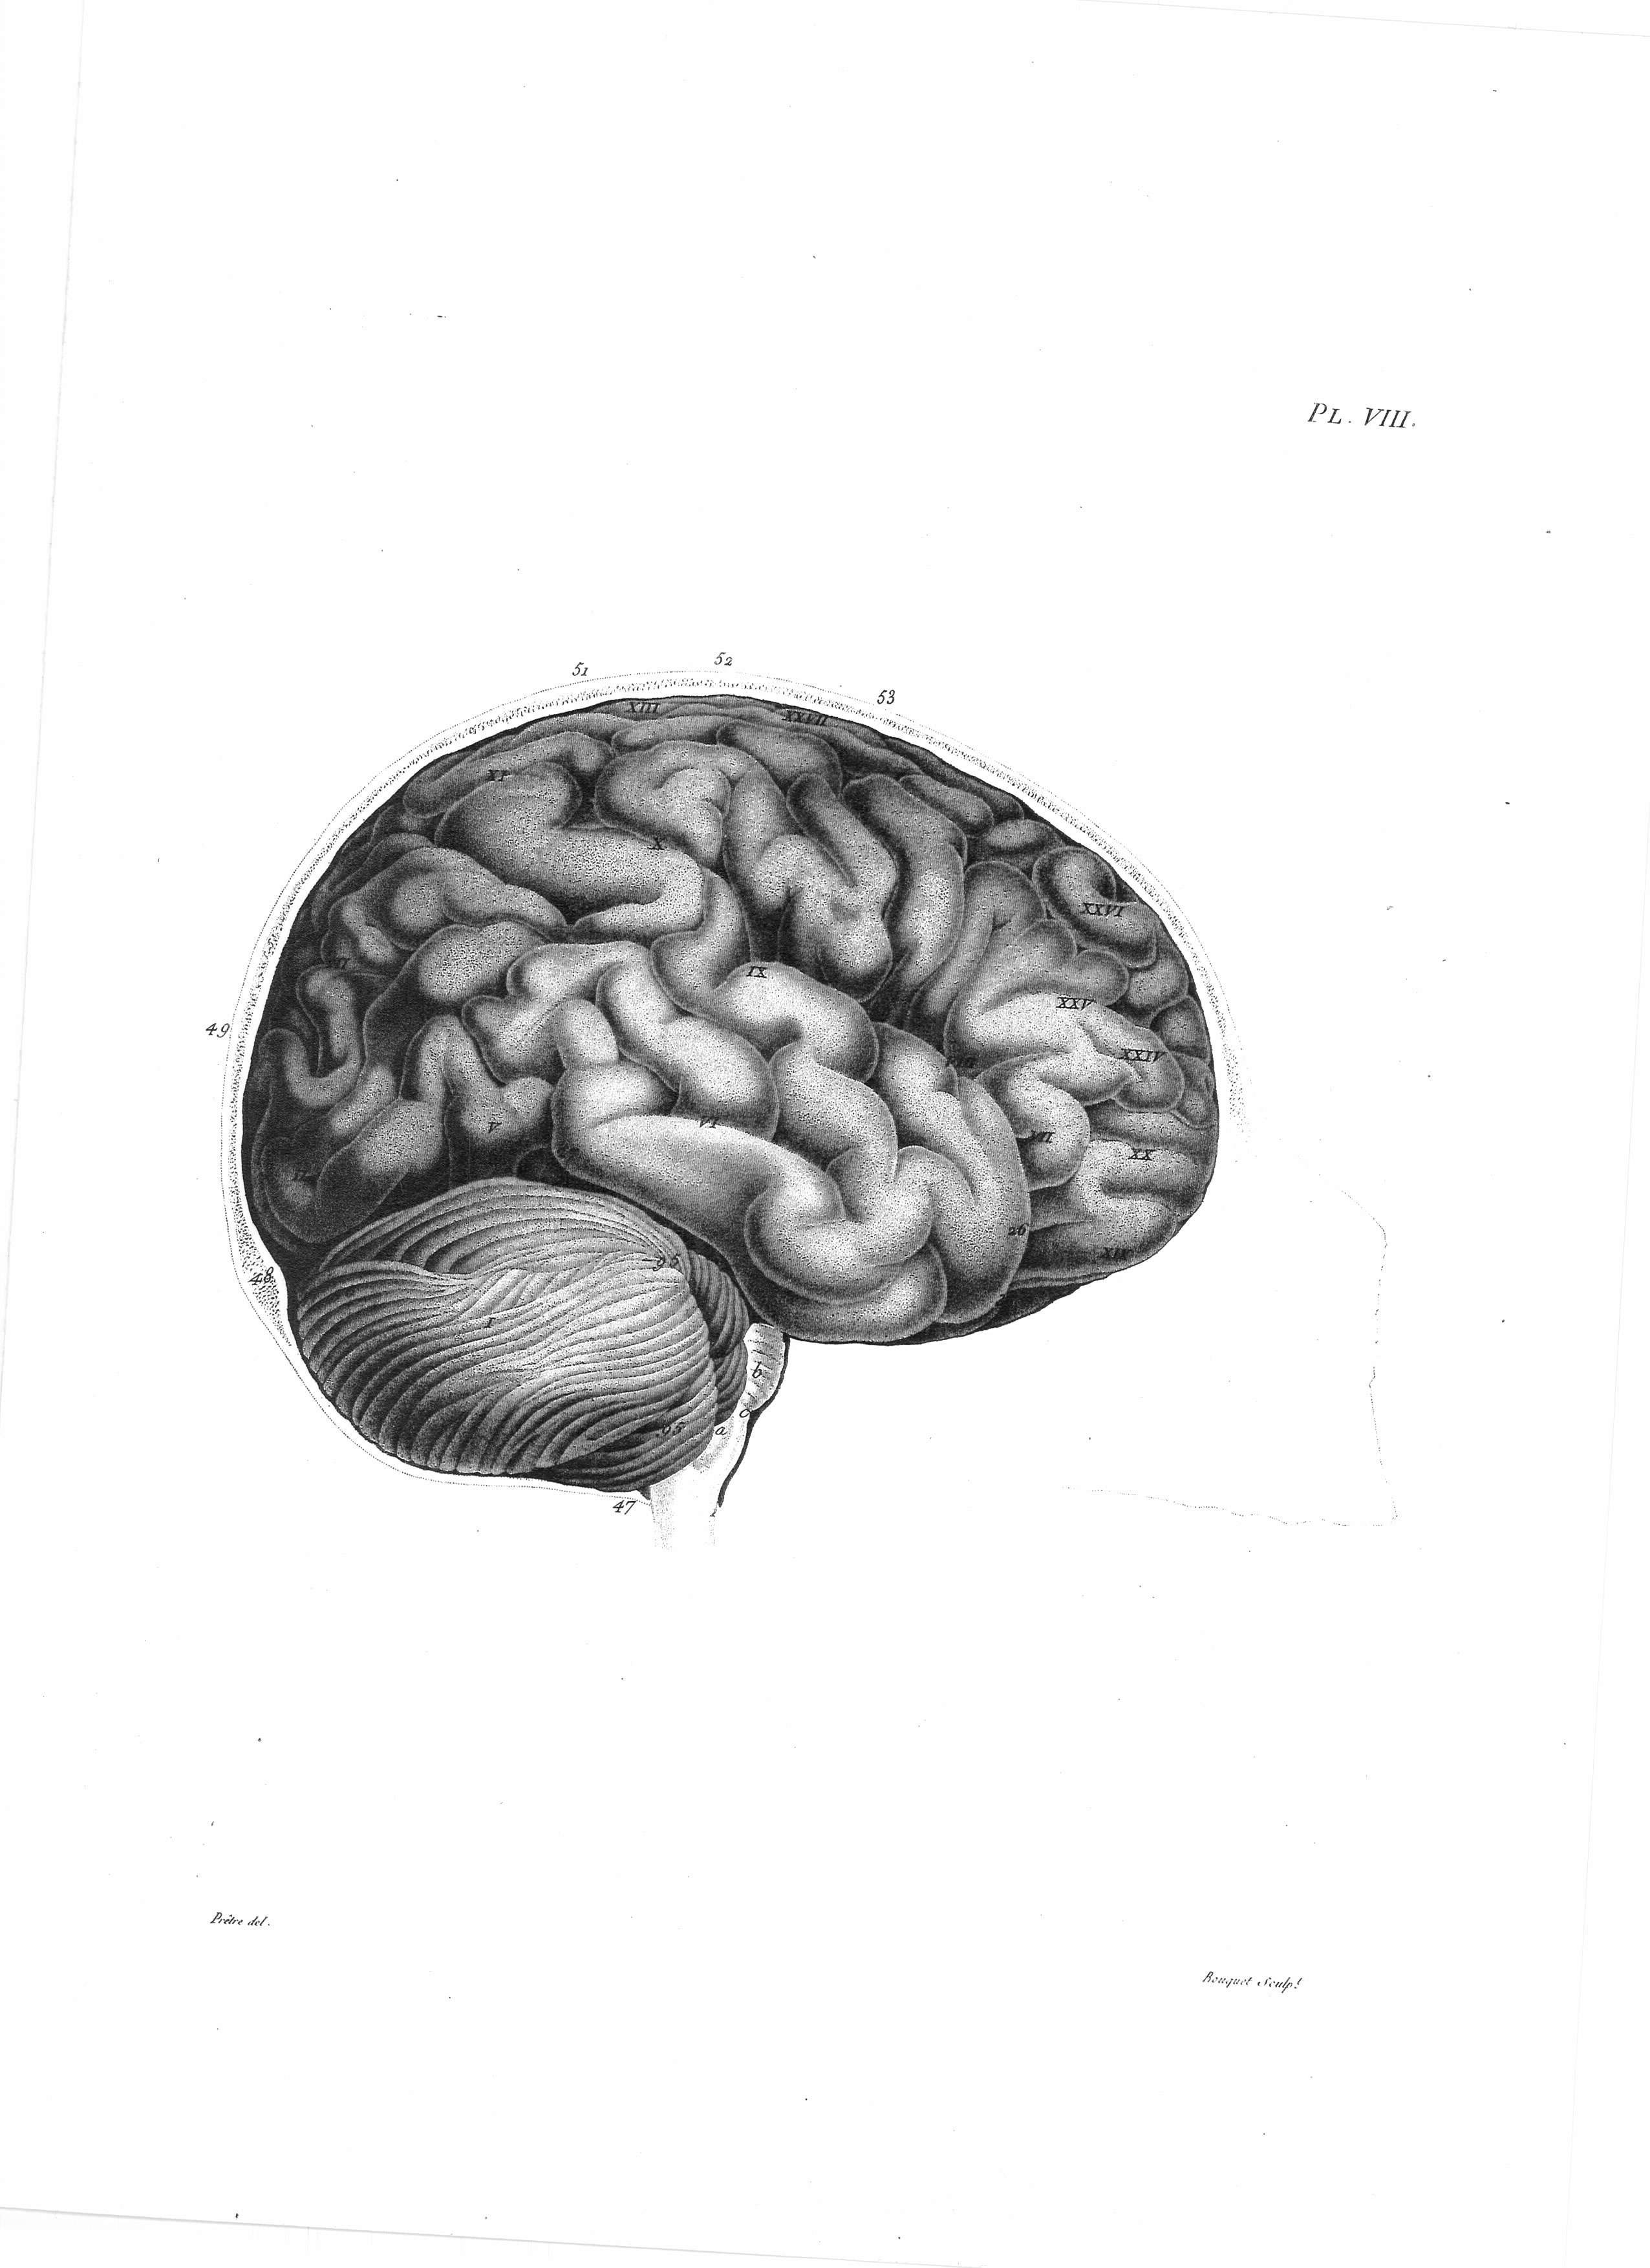

Gall, F. J. (1818). Anatomie et physiologie du système nerveux en général, et du cerveau en particulier, Avec des observations sur la possibilité de reconnoître plusieurs dispositions intellectuelles et morales de l´homme et des animaux, par la configuration de leurs têtes.

Librairie Grecque-Latine-Allemande, Vol. 3, I-XXXV u. 1-379 100 planches.